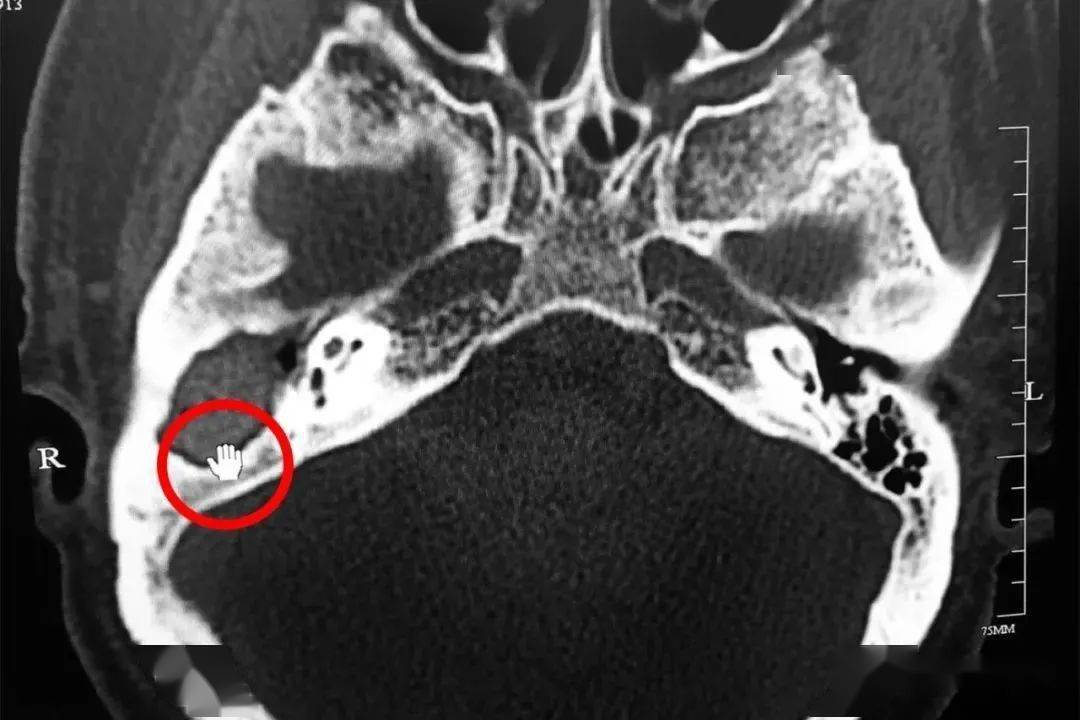

典型病例(右侧听小骨脱位) - 医学影像学讨论版 - 爱爱医医学论坛

ct结果:该结果提示这个病人听骨链有中断的可能.